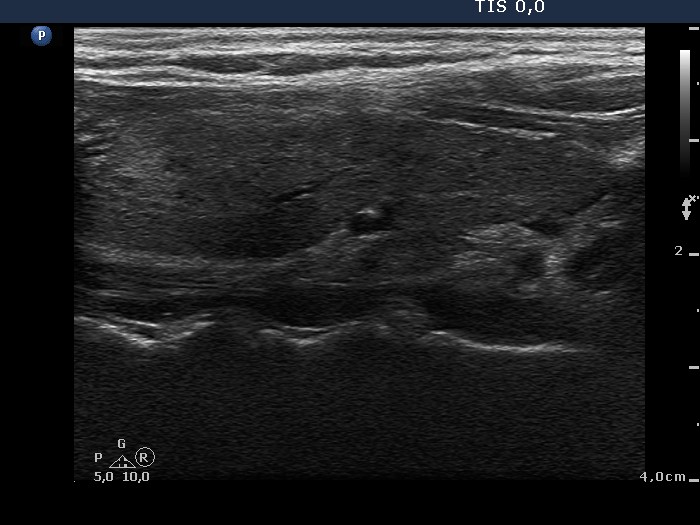

Graves' disease - case 195 (ultrasonographic picture 2)

Right lobe, longitudinal scan. There are multiple hypoechogenic areas in the moderately hypoechogenic lobe.